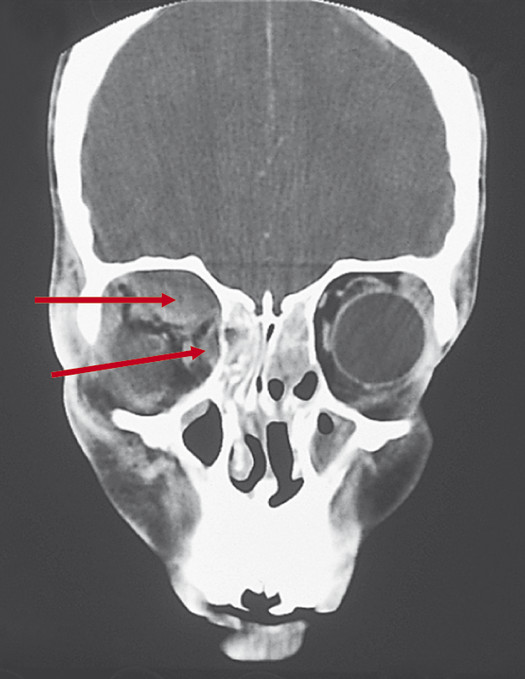

The subperiosteal space is a potential space that lies between the periorbita and the bony orbital walls. The periorbita covers all the bones of the internal orbit. Unlike the periosteum covering bones elsewhere, the periorbita is loosely adherent over the orbital walls, except at the orbital suture lines and along the orbital rims, where it is tightly adherent to the bone. The subperiosteal space is a potential space that can be filled with blood (a subperiosteal hematoma) or pus (a subperiosteal abscess). The periorbita is lifted from the walls of the orbit in a characteristic dome-shaped fashion that is limited by the orbital suture lines (Fig. 19‑2).

The periorbita is dome-shaped below the roof and along the medial wall of the orbit, assuming a configuration limited by the attachment of the periorbita to the frontoethmoidal suture line.